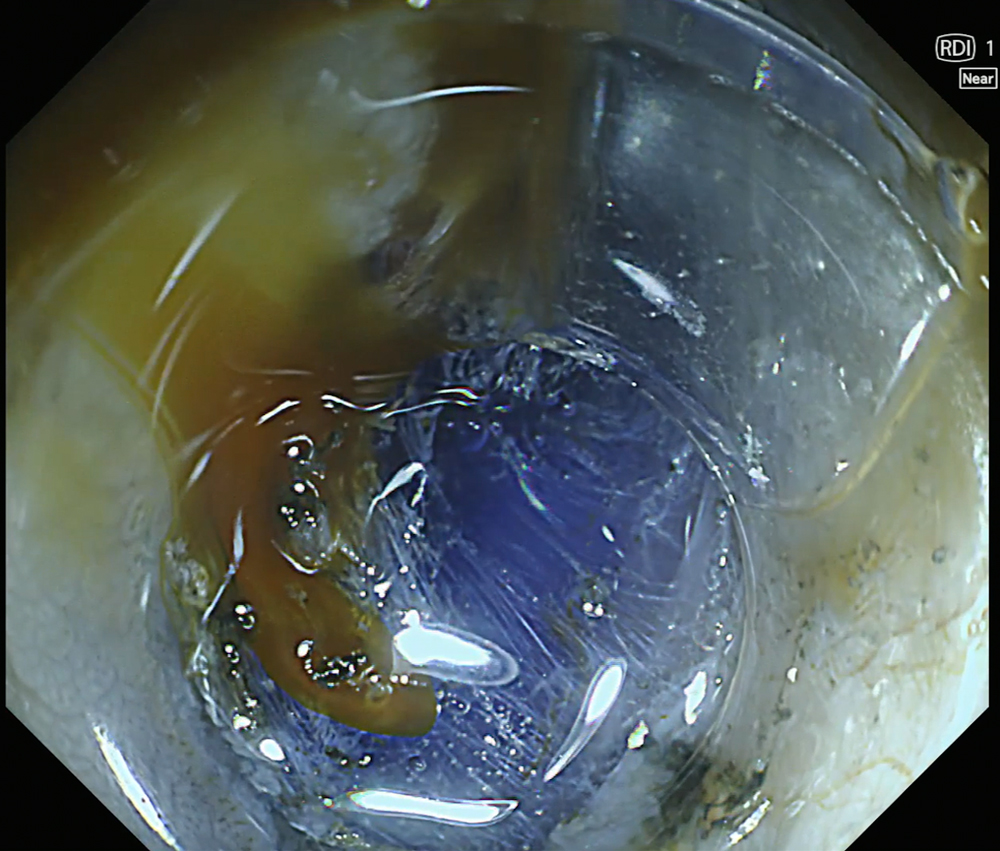

13. Submucosal layer visualization with RDI Mode 1

In RDI mode 1, indigo carmine enhances visualization of the submucosal layer during ESD, allowing clearer identification of the cutting line and facilitating controlled dissection.

This video shows the use of RDI mode 1 during ESD. After activation of RDI mode 1, the bleeding focus is clearly visualized, allowing contact coagulation using a DualKnife J™. In addition, RDI mode 1 combined with indigo carmine enhances visualization of the submucosal layer, facilitating identification of the cutting line during dissection.

In addition, RDI mode 1 combined with indigo carmine improved visualization of the submucosal layer, allowing clearer identification of the cutting line and more controlled dissection.